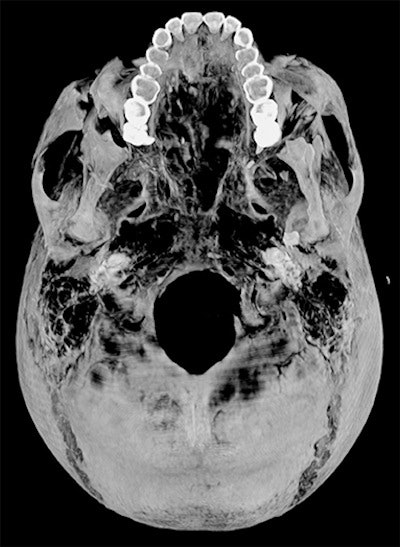

CT revealed details of the head injuries, including wounds that had not been discovered in previous examinations and had been skillfully hidden by the embalmers. The mummy's deformed hands indicate that Seqenenre may have been captured on the battlefield, and his hands were tied behind his back, preventing him from deflecting the fierce attack on his head.

The CT scans, combined with other evidence, suggest the execution was carried out by multiple attackers, which the scientists confirmed by studying five different Hyksos weapons that matched the king's wounds. The study also determined that Seqenenre was about 40 when he died, based on the detailed morphology revealed in the images, providing the most precise estimate to date, according to the authors.

In addition, the investigation revealed details about the mummification of Seqenenre's body. For instance, the embalmers used a sophisticated method to hide the king's head wounds under a layer of embalming material that functioned similarly to the fillers used in modern plastic surgery. This would imply that mummification took place in a real mummification laboratory rather than in a poorly equipped place, as previously interpreted.

Saleem examined the mummy on 4 May 2019. She said she used the usual optimum CT scan parameters, including field-of-view and slice thickness, to provide the best 3D reconstruction. Because of the COVID-19 pandemic, it took several weeks to study the Hyksos weapons stored at the Cairo Egyptian Museum and to correlate them with the injuries by physical inspection of the mummy and on CT scans.